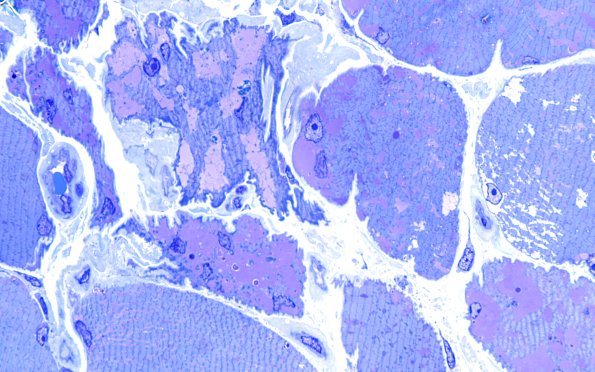

5C5 Muscle (Case 5) Plastic 100X 3

A variety of atrophic fibers with variable levels of stored material are shown. (Plastic sections)